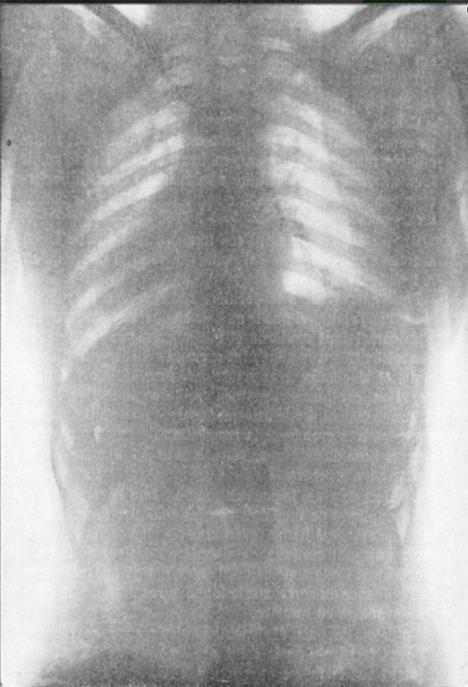

Ovi snimci su nastali još 1908. godine, francuski je doktor Ludovic O'Followell je svojoj je knjizi "Le Corset", između ostaloga, objavio i ove snimke ženskih tela zetegnutih u korsete.

Snimci jasno pokazuju da korset pritiska kičmu i pomera unutrašnje organe. Ovaj lekar je bio i kolumnista i korsetima se bavio u časopisu "Les Dessous Elegance".